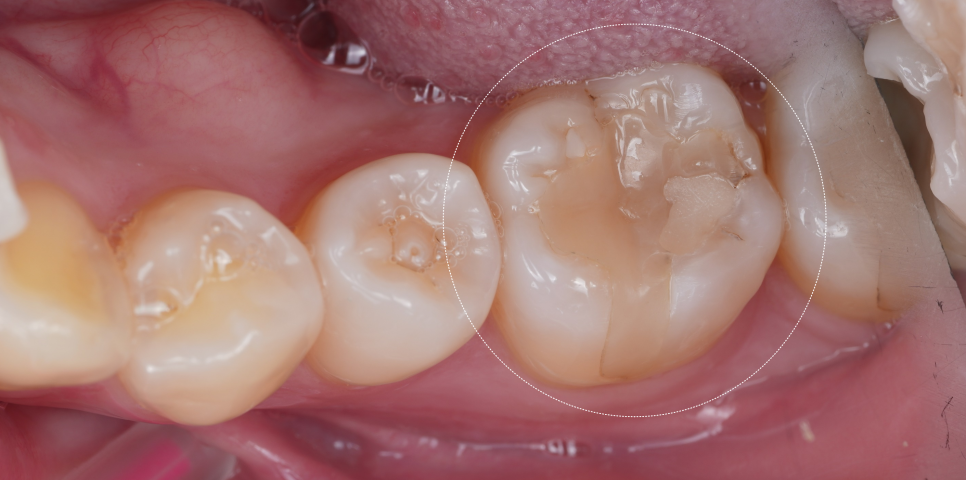

기존 인레이치료 하방으로 틈이 생겼고, 그 틈을 따라 2차 충치가 진행되었다고 합니다.

그래서 B 치과에서 치료를 권했는데.. 해당 부분만 레진으로 덧댄 상태였어요.

촬영일 : 251124

치아 가운데 하얗게 덧댄 것... 보이시죠?

심지어 레진으로 때운 곳도 온전치 않아 보이더라고요..^^;

큐레이를 통해 확인해 봐도 인레이치료 한 경계를 따라 붉은빛으로 문제가 있다는 것을 보여주네요.